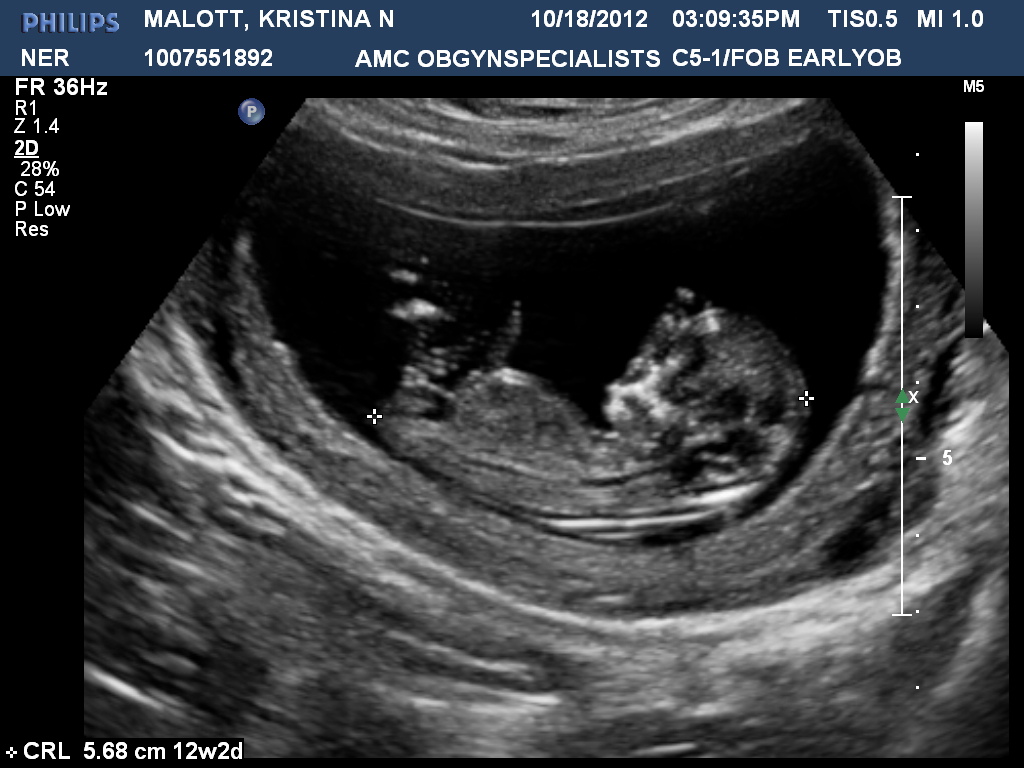

Attachment 5819Attachment 5820

I'd say that the forky thing is a girl nub; a) because most of the forky-looking nubs are girls and b) the nub is lying stright.

boy

A boy!

Mayb girl x

Looks like a girl in the second pic! I don't see anything in the first